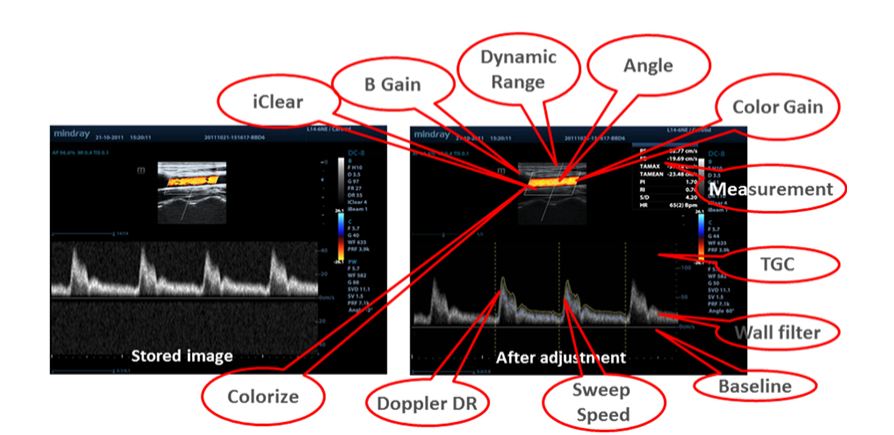

Ham Veriler

Parametre ayarlar?, yorum ekleme ve ?l?ĂŒmler dahil Saklanan g?rĂŒntĂŒlerin i?lem sonras? i?in, tarama s?ras?nda maksimum ĂŒretkenli?e izin vererek optimum esneklik imkan tan?r.